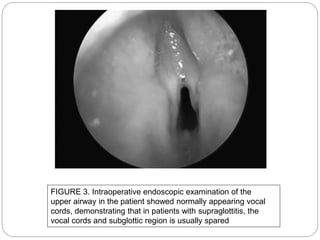

FIGURE 3. Intraoperative endoscopic examination of the

upper airway in the patient showed normally appearing vocal

cords, demonstrating that in patients with supraglottitis, the

vocal cords and subglottic region is usually spared

FIGURE 3. Intraoperativeendoscopic examination of the upper airway in the patient showed normally appearing vocal cords, demonstrating that in patients with supraglottitis, the vocal cords and subglottic region is usually spared